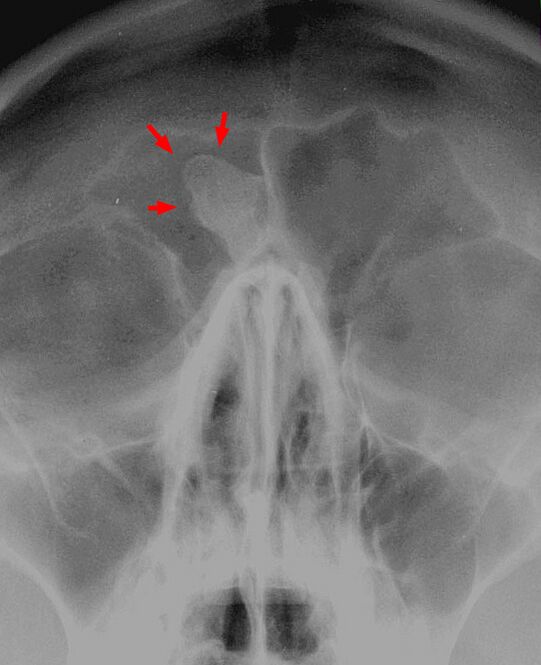

Твёрдые экзостозы встречаются нередко на костях черепа, лица[3] и таза; в последнем случае они могут сильно затруднять родовой акт (так называемый остистый таз)[2].

Диагностика

Диагноз остеомы ставят на основании клинико-рентгенологических данных. Дифференциальный диагноз между хроническим остеомиелитом и остеогенной саркомой легко установить на основании рентгенологической картины и течения заболевания.